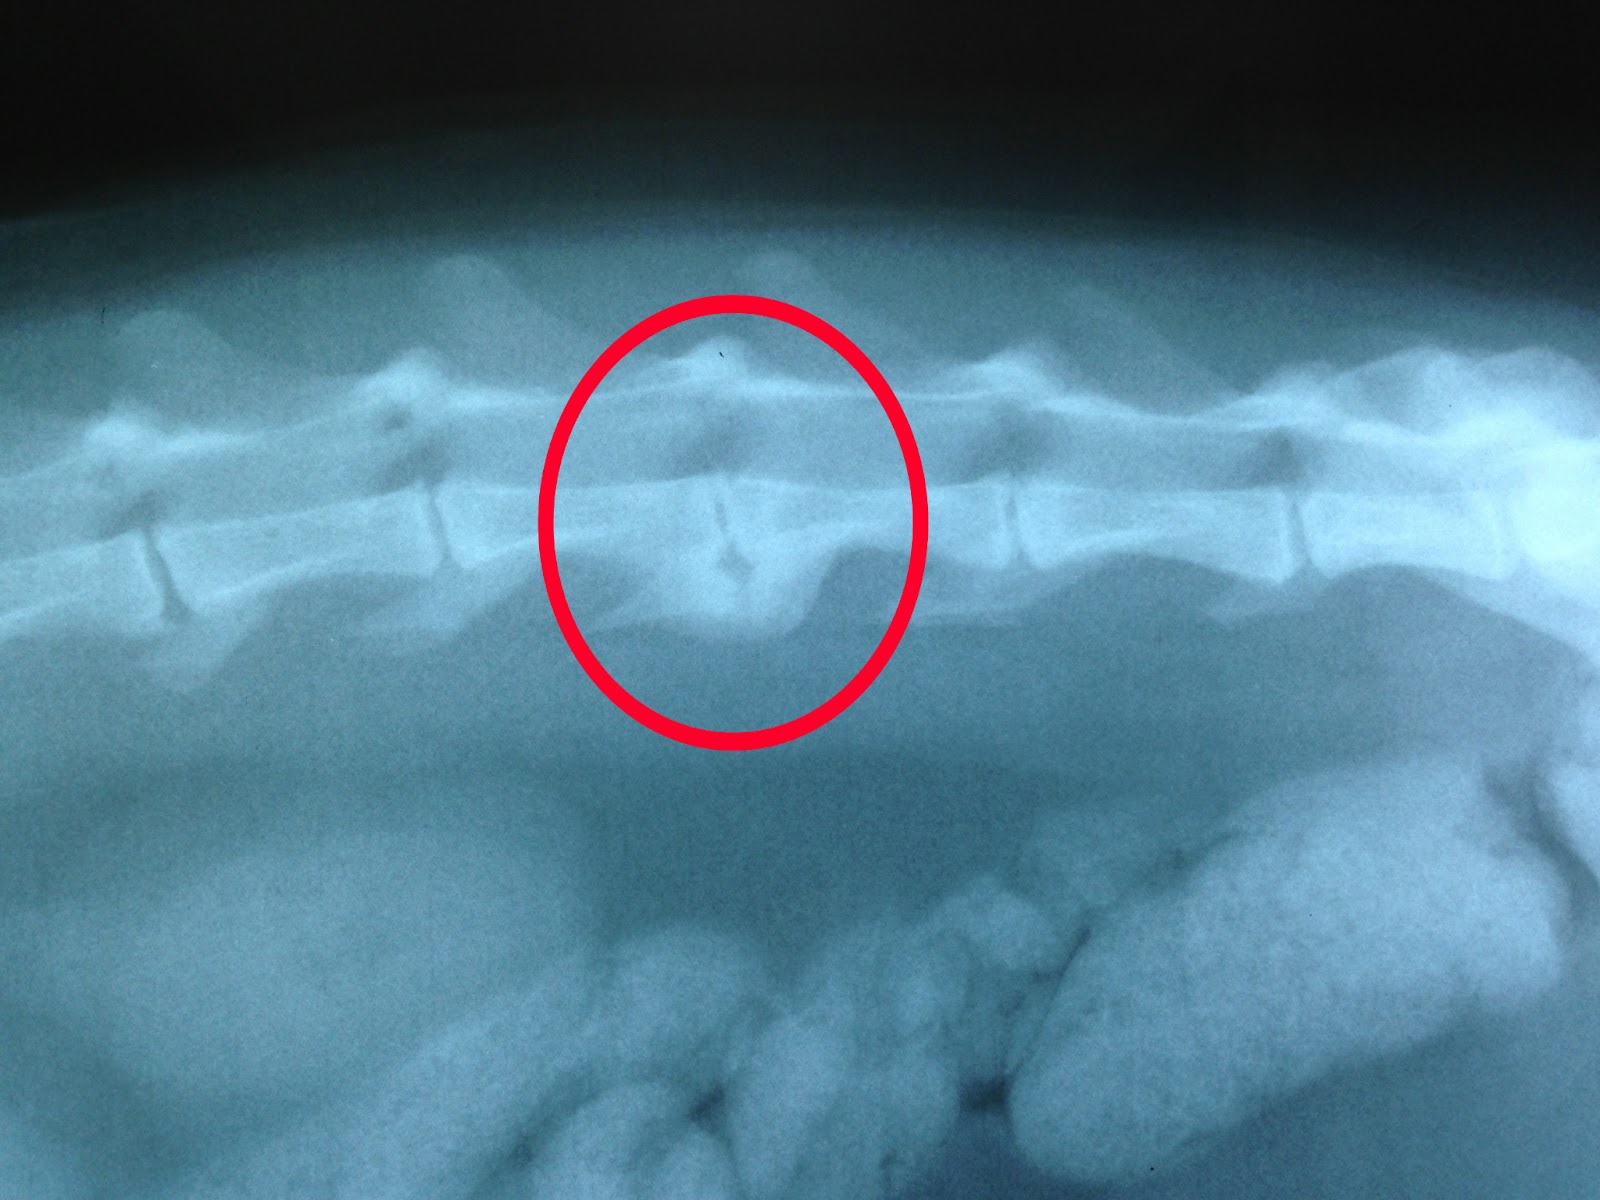

Болезнь дисков у собак